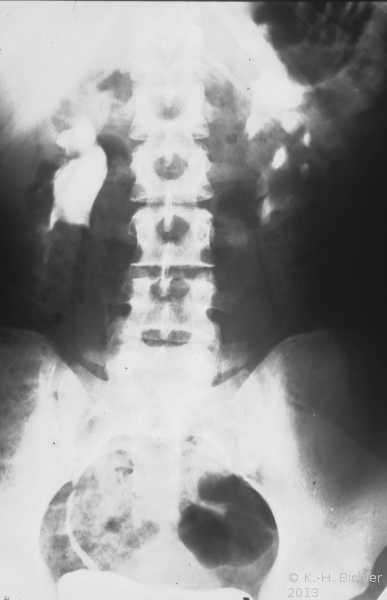

• Abbildung 17: Ureterabgangsstenose mit ausgedehnter Hydronephrose links

1. Ausscheidungsurogramm stumme Niere links (schwacher nephrographischer Effekt)

2. Spätaufnahme (AUR): Erheblich dilatiertes Nierenbecken links